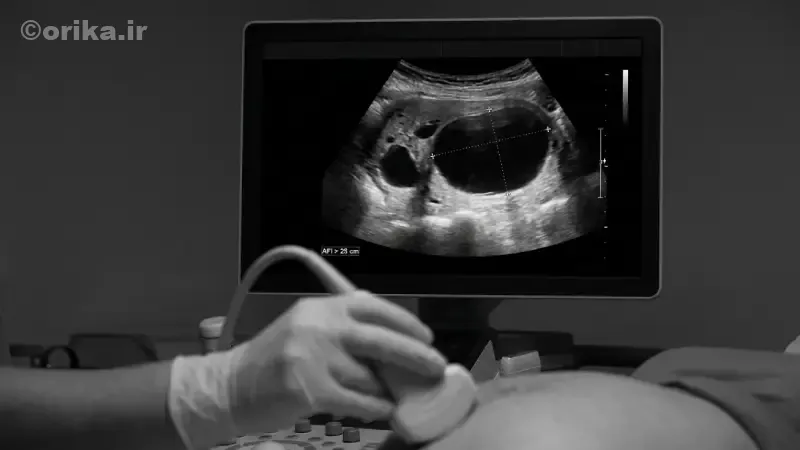

حجم مایع آمنیوتیک در طول بارداری بهطور طبیعی تغییر میکند. بیشترین مقدار آن معمولاً در هفتههای ۳۲ تا ۳۶ بارداری مشاهده میشود. پزشکان برای اندازهگیری از شاخص AFI (Amniotic Fluid Index) استفاده میکنند. AFI طبیعی بین ۸ تا ۲۴ سانتیمتر در نظر گرفته میشود. مقادیر بالاتر نشانه افزایش مایع آمنیوتیک هستند. ارزیابی باید در کنار شرایط بالینی انجام شود. تصمیمگیری صرفاً بر اساس یک عدد منطقی نیست.

تشخیص عمدتاً بر اساس سونوگرافی انجام میشود. اندازهگیری AFI یا پاکت عمقی معیار تشخیصی است. بررسی رشد جنین الزامی است. آزمایش قند خون مادر انجام میشود. در موارد خاص، بررسی ژنتیک توصیه میشود. تشخیص زودهنگام اهمیت زیادی دارد. تکرار سونوگرافی برای تأیید لازم است.

| شدت افزایش مایع | AFI (سانتیمتر) | خطرات اصلی | رویکرد درمانی |

|---|---|---|---|

| خفیف | 24-29 | معمولاً بدون عارضه | پایش دورهای |

| متوسط | 30-34 | زایمان زودرس | بررسی علت |

| شدید | ≥35 | عوارض زایمانی جدی | درمان فعال |